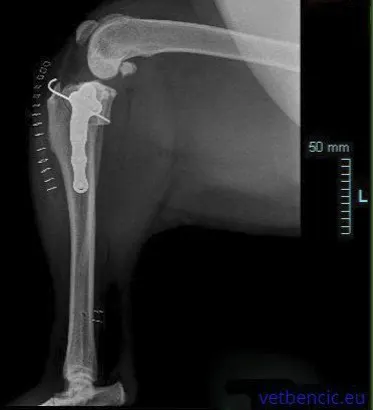

Vrlo složeni operativni zahvat koji uključuje odsijecanje cijelog bolesnog zgloba. Glava bedrene kosti se zamjenjuje metalnim implantatom, a zglobna čašica plastičnim ili metalnim implantatom. Implantati su pričvršćeni za kost uz pomoć koštanog implantata ili imaju spužvastu ovojnicu kroz koju kost može prodrijeti. Umjetni kuk se najčešće ugrađuje velikim psima, ali se može ugraditi i malim psima i mačkama. Kod pacijenata kod kojih je potrebna intervencija na oba kuka, intervencije se nikad ne rade istodobno zbog većeg rizika od komplikacija. Uspješnost ove intervencije je 90-95%, a nakon nekoliko dana pacijenti normalno hodaju. Većini pasa vraća punu aktivnost.